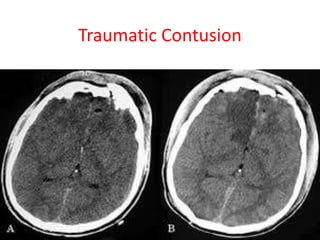

Traumatic Contusion